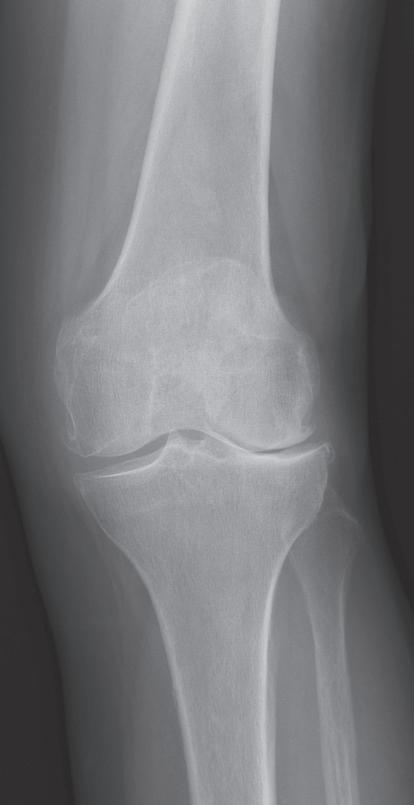

(předozadní a bočná). Na rentgenovém snímku se gonartróza zpočátku projevuje přihrocením interkondylické eminence a subchondrální sklerózou v místě přetížení, později zúžením, případně až zánikem kloubní štěrbiny, vznikem osteofytů, pseudocyst a případnou úhlovou deformitou. Dle nálezu rovněž klasifikujeme stupeň gonartrózy podle Kellgrena-Lawrence (viz kap. 17, obr. 19.4), což má praktický význam v indikaci farmakoterapie i balneoterapie.

Obr. 19.4: Stupně gonartrózy dle Kellgrena-Lawrence na rtg snímku, I.–IV. stupeň (a–d)

a) b) a) b) c) d)